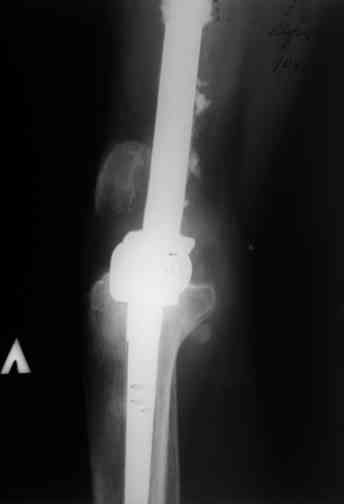

Этот стиль мне полностью приемлем и понятен. Наверно я бы поступил также. Но статистика упрямая вещь. Сколько у тебя или у другого врача опыта по замещению дефектов бедра? У меня за 25 лет работы 3, и еще около 15 случаев удлинения бедра. Случай у тебя очень сложный. Если Вы выбираете Илизаровскую методику то надо на в/з хорошую дугу, не менее 4-5 спиц с напайками.Стержни хороши когда кость не измучена и на 2-4 месяца. Здесь аппарат на 6-8 месяцев. Если есть желание я только за, и

Прикрепляю пример замещения дефекта бедра 20 см, после резекции по поводу опухоли, эндопротеза Сиваша, вялотекущего остеомиелита со свищами в течении 3 лет. Получилось хорошо и всего за 6 месяцев в аппарате. Колена не было. У Вас случай сложнее. Это было в 1998г. Я работал в ЦИТО и у меня было 4 больных, я занимался им с утра до ночи. Сейчас 60 больных и операций в нашем отделении 25-30 в неделю.Если могу чем помочь - нет проблем.